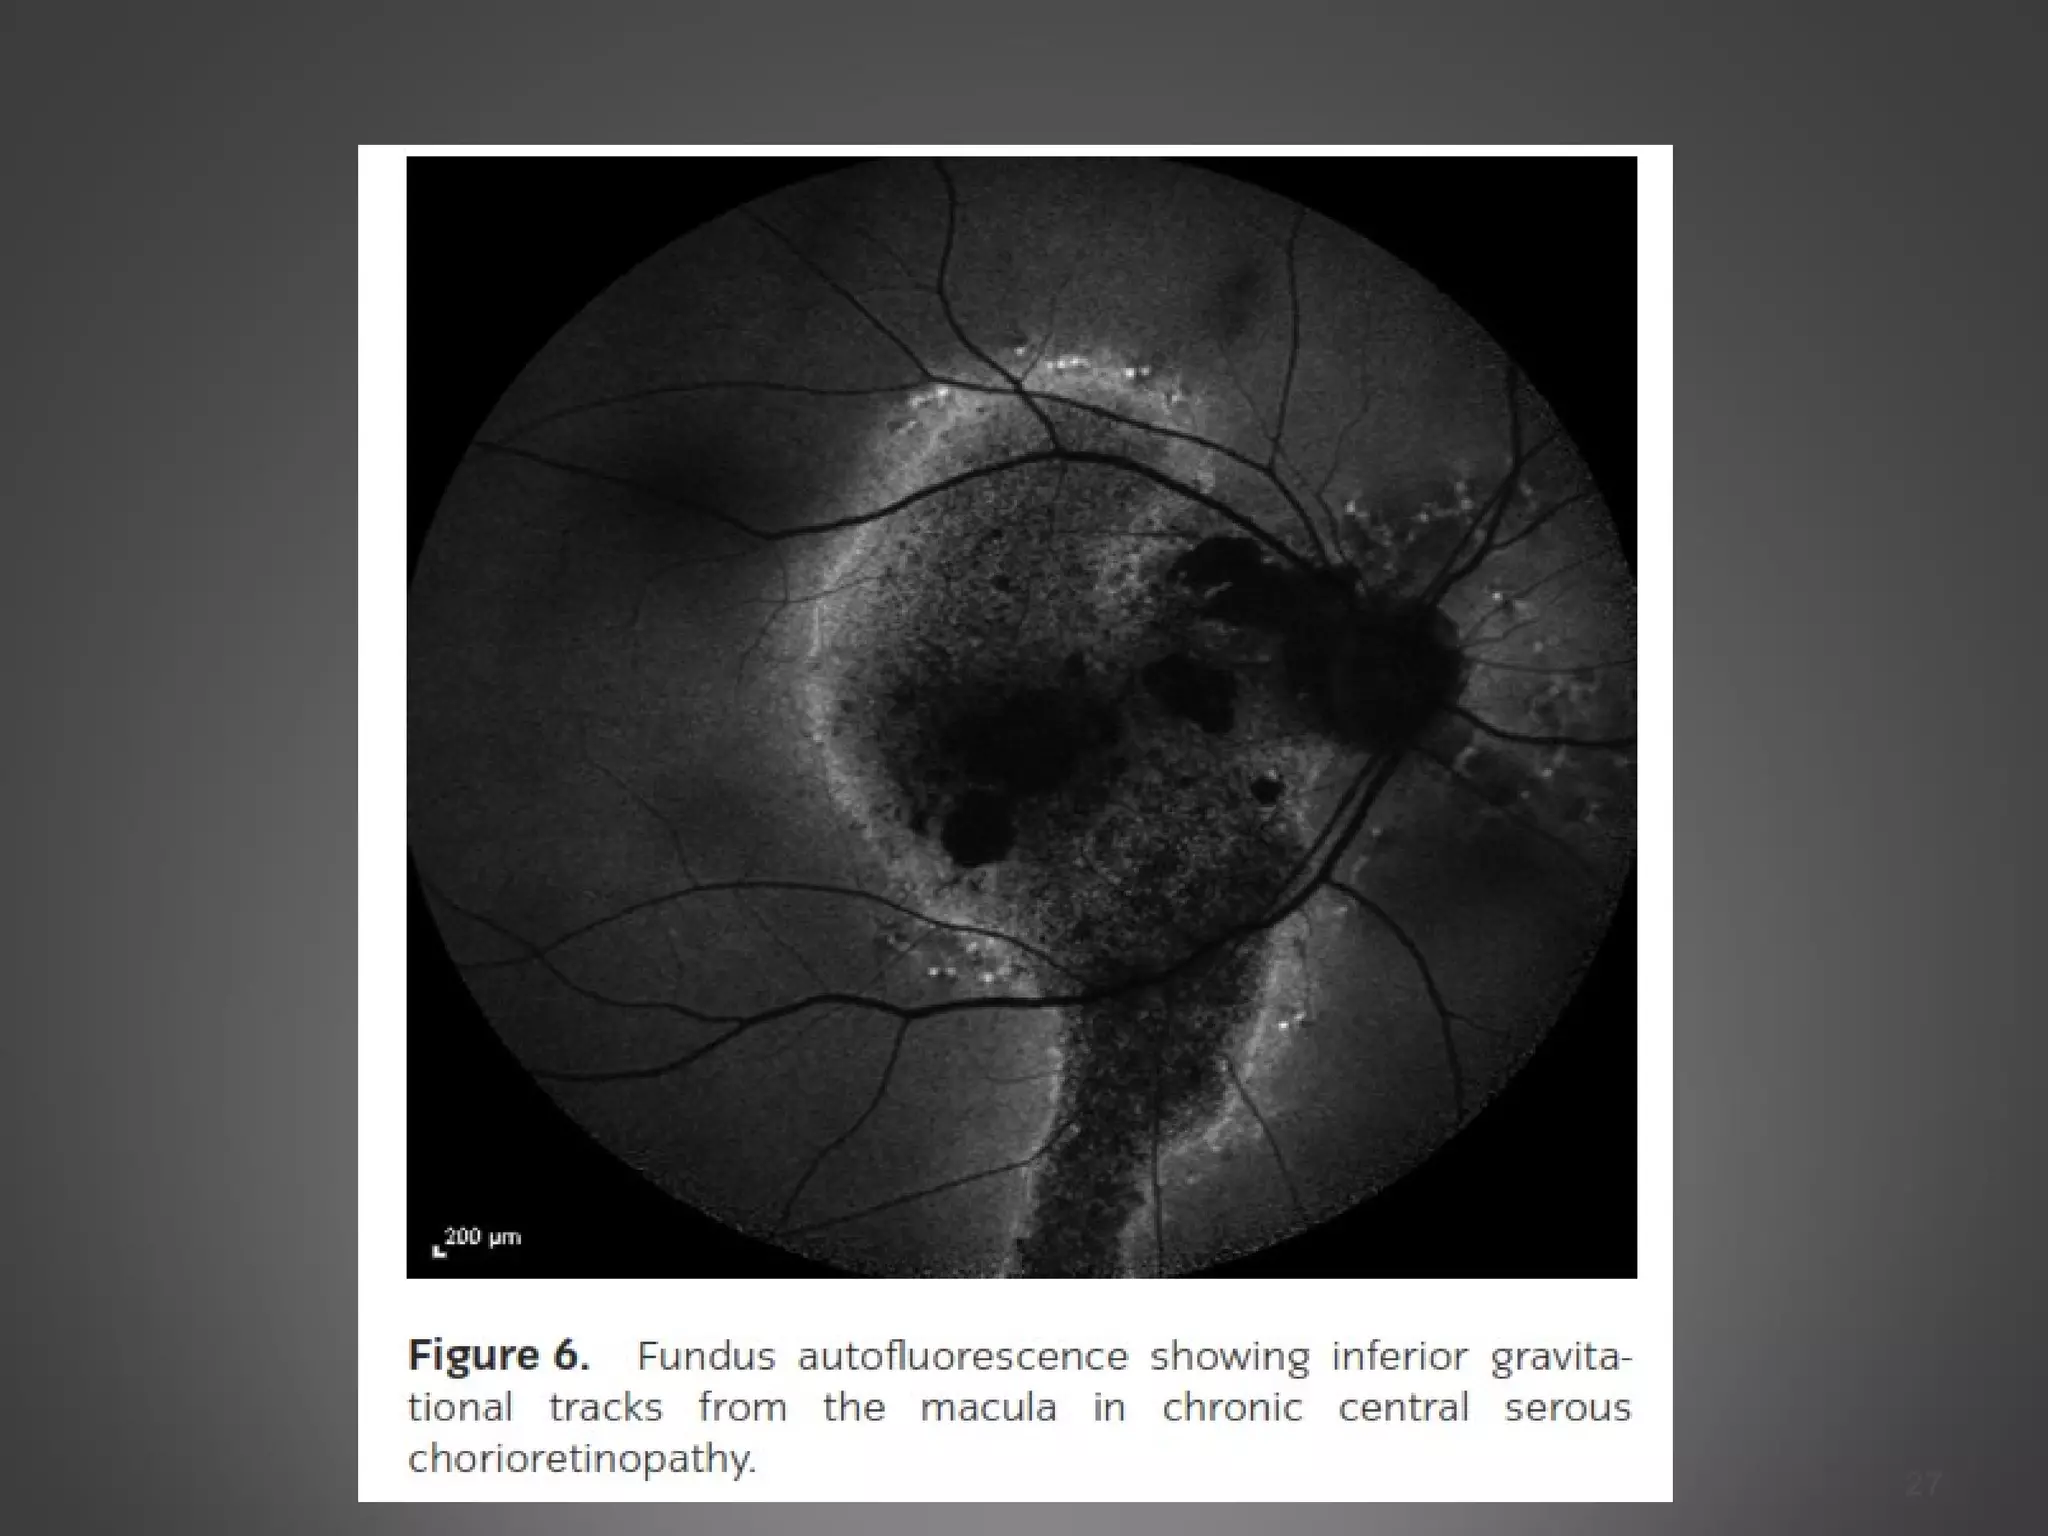

Fundus autofluorescence

 FAF typically shows hypofluorescence at the leakage point and

over the area of neurosensory detachment due to blockage by

subretinal fluid.

The subretinal yellow dots observed clinically might demonstrate

hyperfluorescence

In chronic-recurrent CSC,hyperfluorescence is common in areas

of residual neurosensory detachment.

Fundus autofluorescence  FAFtypically shows hypofluorescence at the leakage point and over the area of neurosensory detachment due to blockage by subretinal fluid. The subretinal yellow dots observed clinically might demonstrate hyperfluorescence In chronic-recurrent CSC,hyperfluorescence is common in areas of residual neurosensory detachment. Other tests Multifocal ERG has been used to identify focal regions of decreased retinal function, even in asymptomatic or clinically inactive eyes. Microperimetry has also shown that, despite clinical resolution of CSR, there is lower retinal sensitivity in the macula even once visual acuity returned to 20/20 26